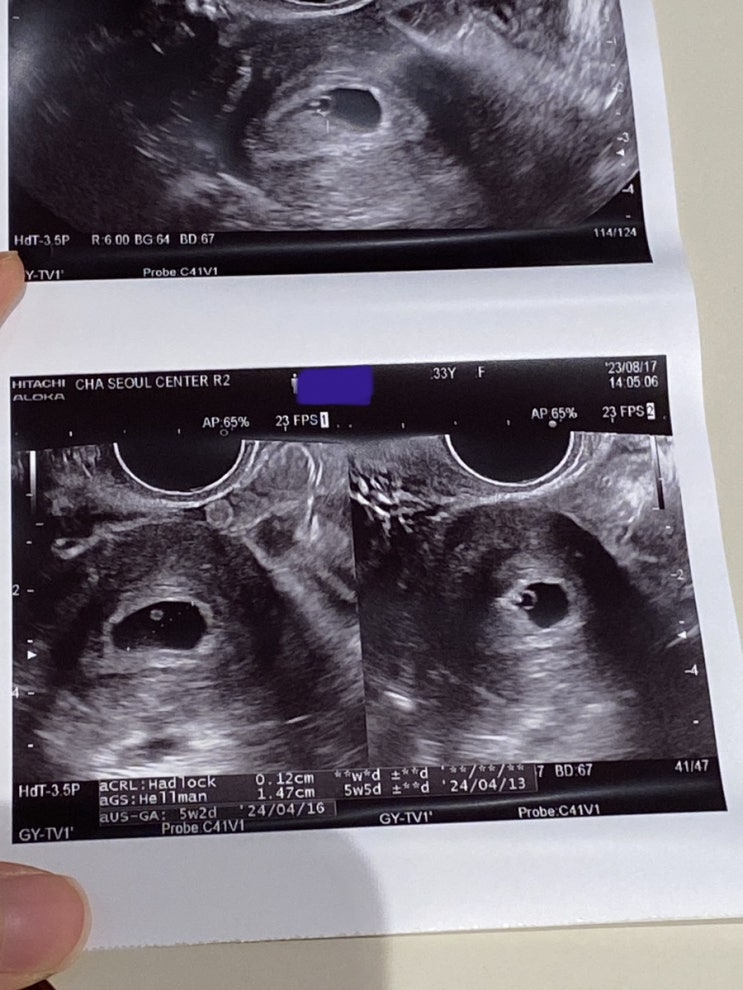

[2세준비] 10. 서울역차 심장소리 듣고 이제 졸업 (6주차 심장소리 / 8주차 심장소리 / 드디어 졸업 / 마지막 프롤루텍스!!!)

보건소방문(결혼기념일즈음에 방문해서 건강검진/난소AMH/정자검사 진행) 배란테스트기로 자연임신 시도...

[2세준비] 9. 서울역차 시험관1차 (동결이식 1차성공 / 3차피검사 / 첫초음파 확인 / 심장반짝임확인 / 임신확인서)